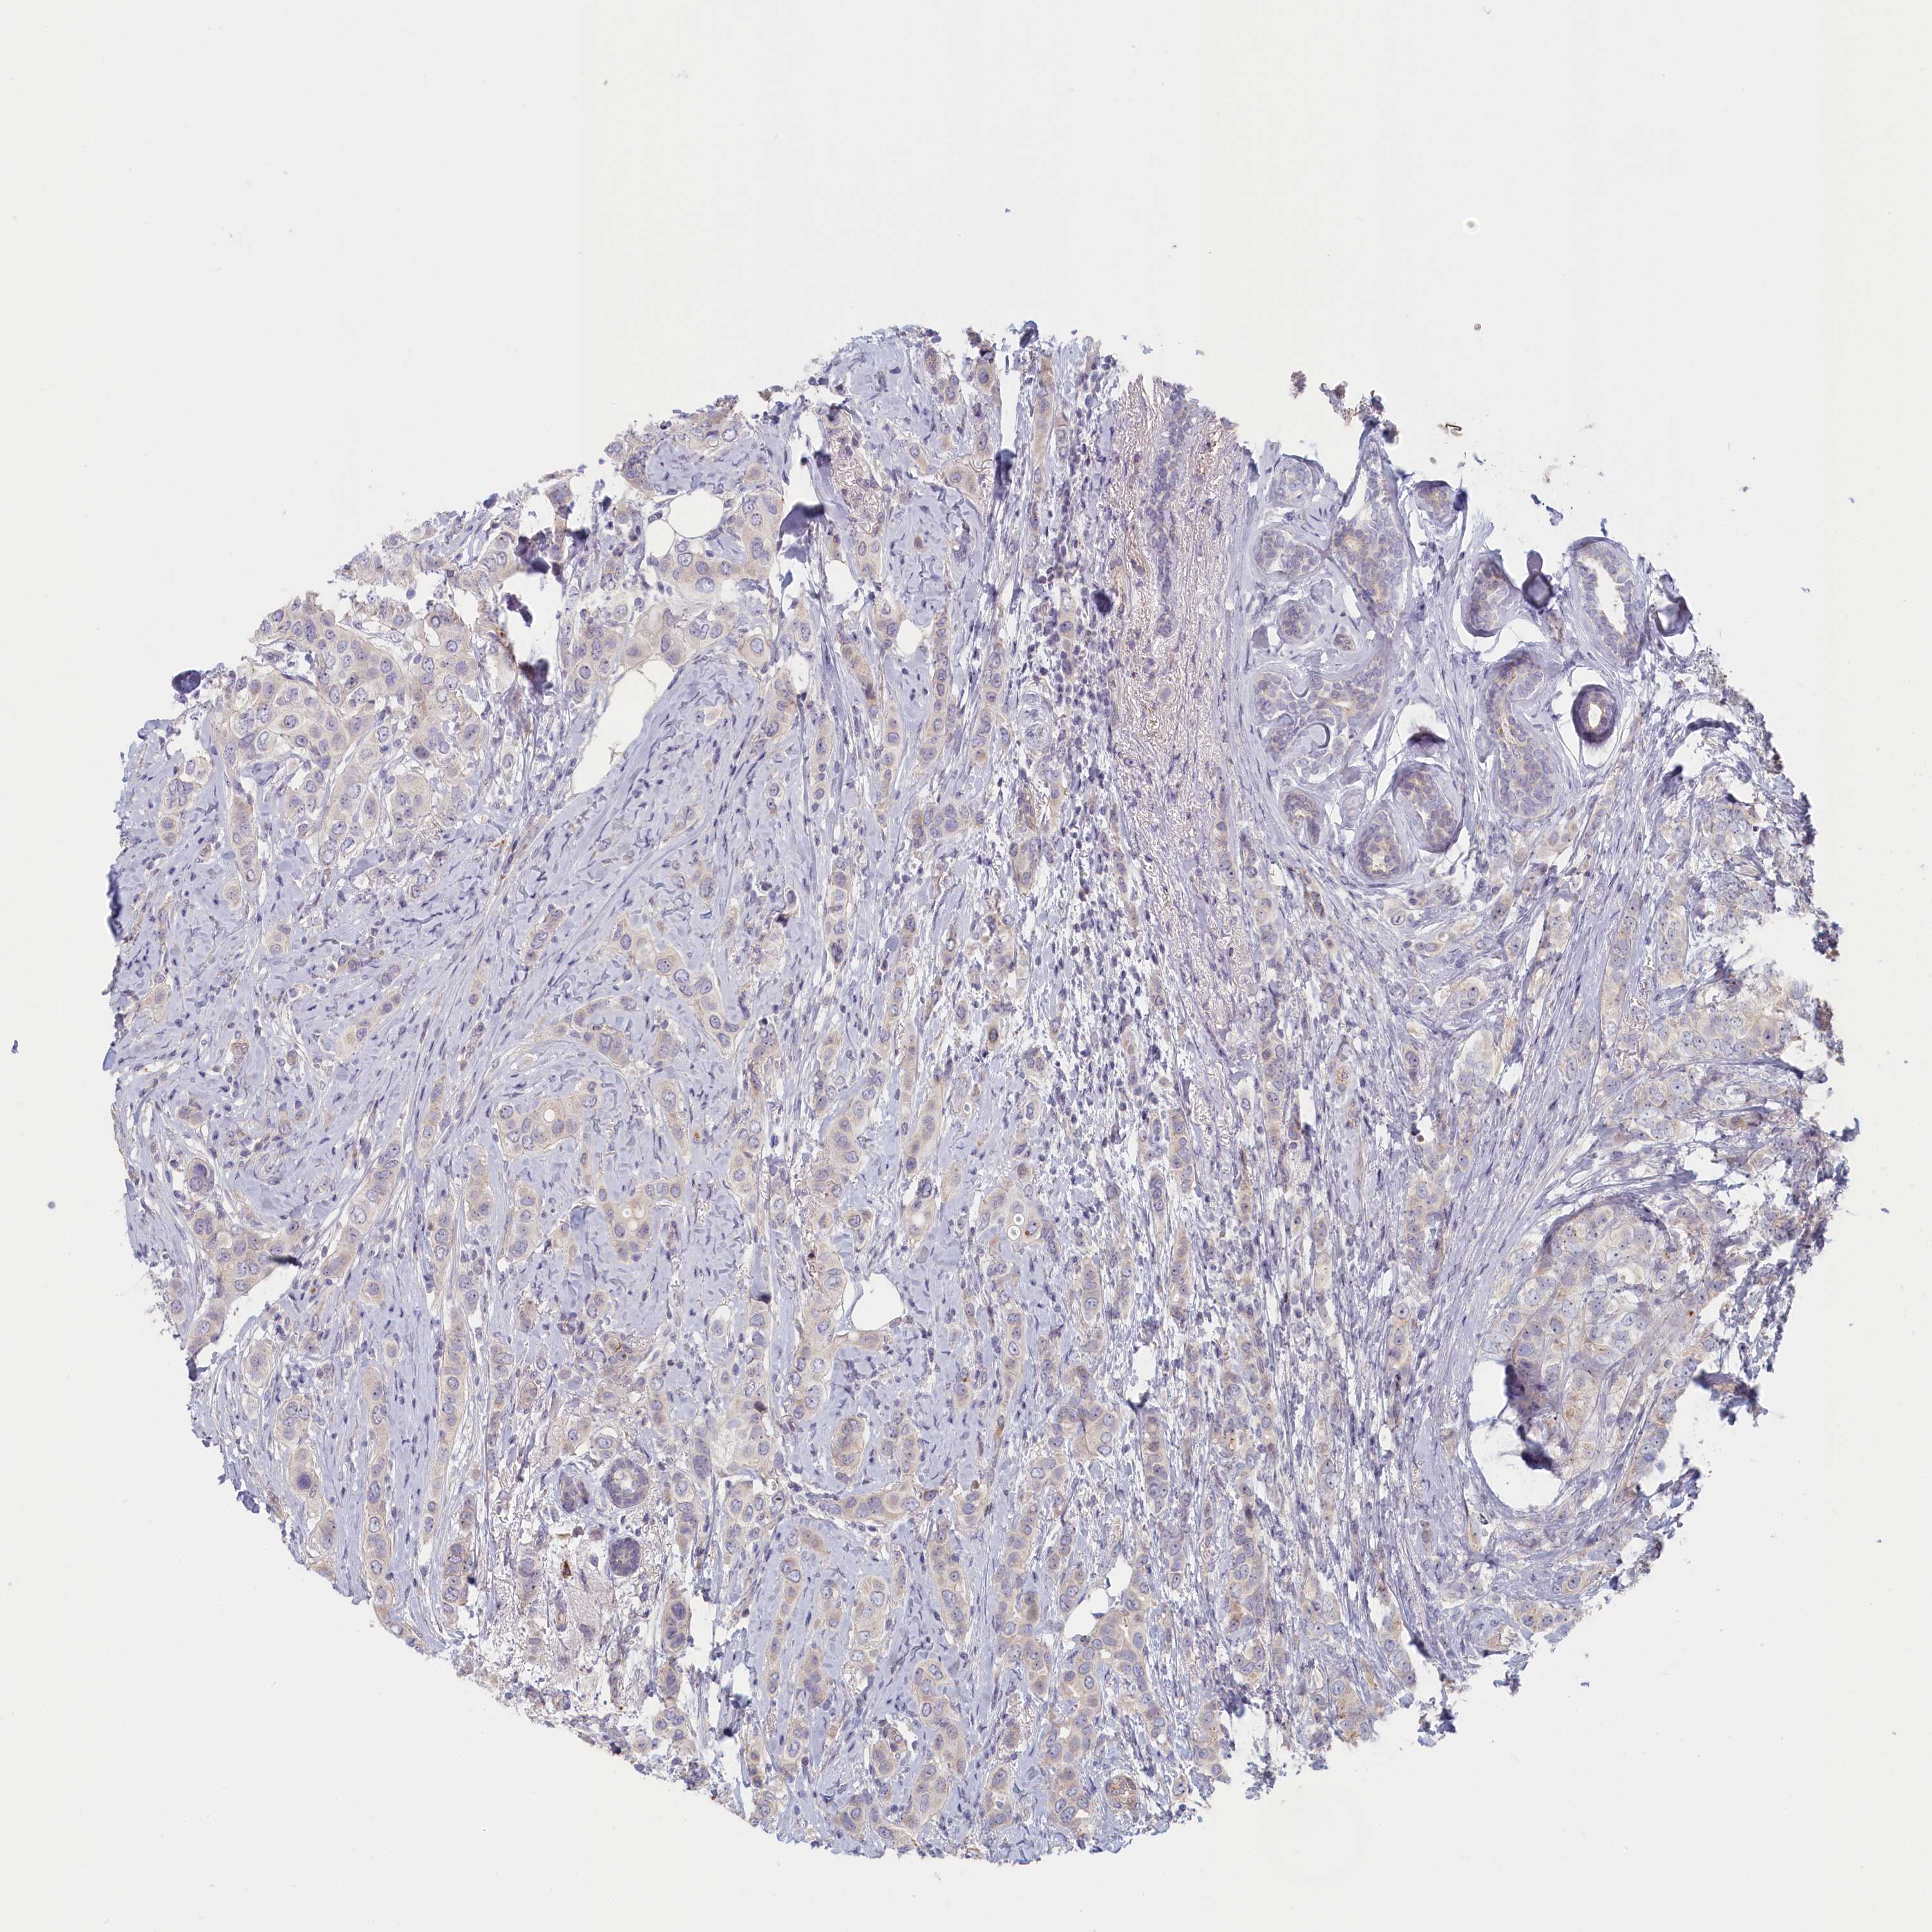

CANCER BREAST CANCER Show tissue menu

BRCA TCGA BRCA VALIDATION PROTEIN EXPRESSION

ANTIBODIES

AND

VALIDATION